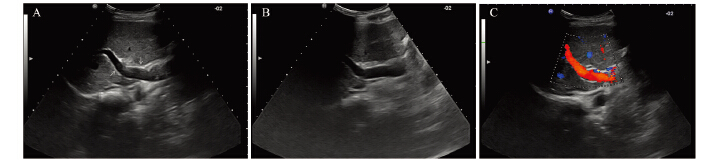

根据以上标准分级,A组病例癌栓Ⅰ级15例、 Ⅱ级11例、Ⅲ级8例,B组病例癌栓Ⅰ级13例、Ⅱ级 11例、Ⅲ级7例。 两组患者的门静脉癌栓分布情况 差异无统计学意义(χ2=0.071,P=0.965),见图 1。

|

| A: Grade Ⅰ PVTT,left branch of PVTT; B: Grade Ⅱ PVTT,main and right branch of PVTT; C: Grade Ⅲ PVTT,main and right branch of PVTT; D:Grade ⅢPVTT,left branch of PVTT; PVTT: portal vein tumor thrombosis 图 1 Ⅰ、Ⅱ、Ⅲ级癌栓声像图 Figure 1 Ultrasonogram of GradeⅠ,Ⅱand Ⅲ PVTT |